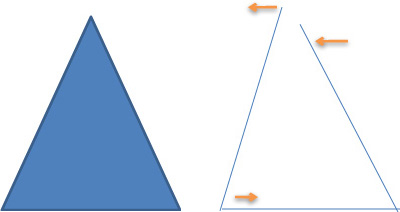

4. Becken Vergleich mit einem Gleichschenkligen Dreieck. |

Diese seitliche Verschiebung hat zur Folge, dass der Schenkel mit dem vergrösserten Winkel zum Becken nach innen drückt. Die Gegenseite drückt durch den kleineren Winkel die Hüftkugel noch oben. Dem wird dann vielmals durch auswärtsdrehen dieses Fusses dagegengehalten. | Beinstellungsveränderung Durch seitliche Hüftverschiebung, hier auf der Abbildung Mitte zu sehen ist, erfolgt eine scheinbare wie auch messbare längen Abweichungen. Grund dafür ist die seitliche Beckenverschiebung die zu einer Schenkel Winkel Veränderung zum Becken führt und somit den scheinbare längen Unterschied verursacht. |